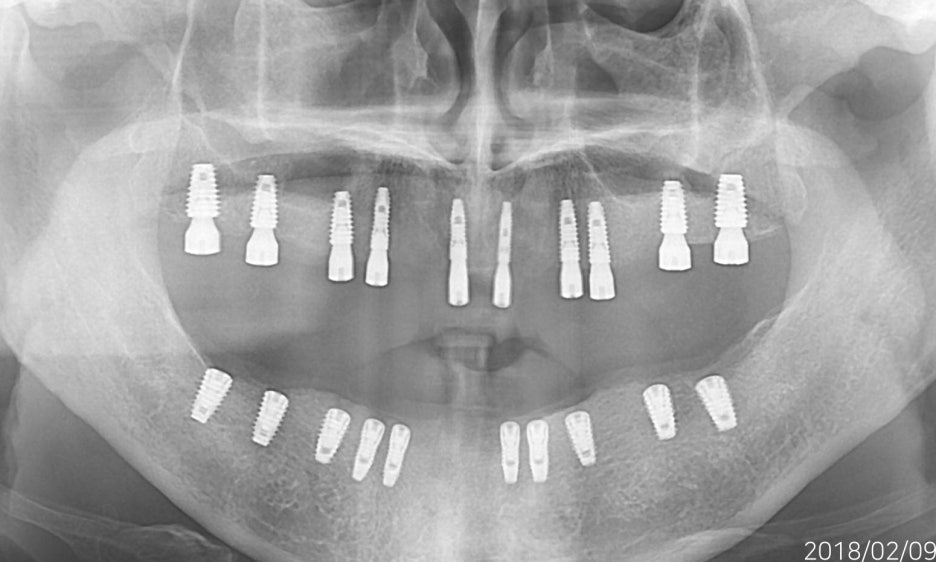

무치악환자를 위한 전악임플란트

전악임플란트 중점 치료

<참고이미지> 무치악 환자의 임플란트 치료 사례 / 환자에 따라 치료결과는 다를 수 있으며 임플란트 주위염 등이 발생할 수 있습니다.

무치악 환자에게 적용시 치아의 기능을 일정수준으로 회복할 수 있는 치료입니다.

<치료의 이해를 돕기위한 참고이미지>

20.09.19 경과체크 / 무치악 임플란트 치료 / 환자에 따라 치료결과는 다를 수 있으며 임플란트 주위염 등의 부작용이 발생할 수 있습니다.

기능의 회복은 물론 심미적인 목적도 충족 시킬 수 입니다.

치아의 상태와 잇몸뼈 상태를 고려한 식립

필요한 개수만큼 식립하여 경제적으로 치료 받을 수 있습니다.